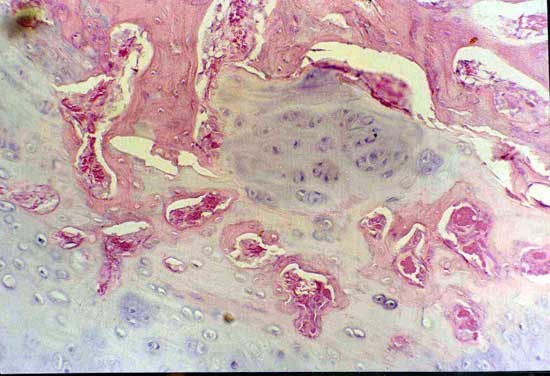

4周软骨钙化                            骨小梁形成

髓腔形成                              X线4周(BM vs MSC)